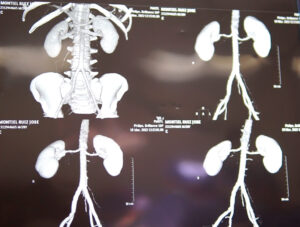

Después de todas las pruebas y análisis realizados por el equipo multidisciplinario del HGZ No. 49 del IMSS, la respuesta fue positiva y el pasado 27 de septiembre se realizó la cirugía de trasplante renal con la que su calidad de vida mejorará invaluablemente.

Gámez Gámez señaló que el procedimiento tuvo una duración aproximada de cinco horas y transcurrió sin complicaciones, además de que una vez realizada la intervención, el riñón trasplantado comenzó a trabajar de manera adecuada y posterior a las primeras 72 horas la función renal ya se encontraba en niveles normales.

“La evolución fue favorable, nosotros lo trasplantamos el 27 de septiembre y para el viernes, para el día 30 ya tenía cifras de una función renal normal, con sus niveles de creatinina normales. La evolución fue favorable, no tuvimos ningún incidente durante su intervención ni durante su recuperación, todo fue satisfactorio y lo dimos de alta este 3 de octubre por la tarde”